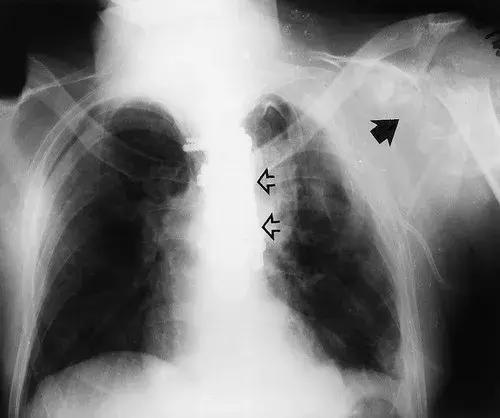

图3:患者28岁,T8截瘫,肩部神经性骨关节病。 (a)胸部X线片显示左盂肱关节实质性破坏(实线箭头)。 注意脊柱固定硬件(空心箭头)。 (b)轴向CT扫描显示由低衰减液体扩张的关节内衬的骨质碎片(箭头)。 (c)颈椎的T2加权自旋回波MR图像(2,400 / 80)显示广泛的空洞。